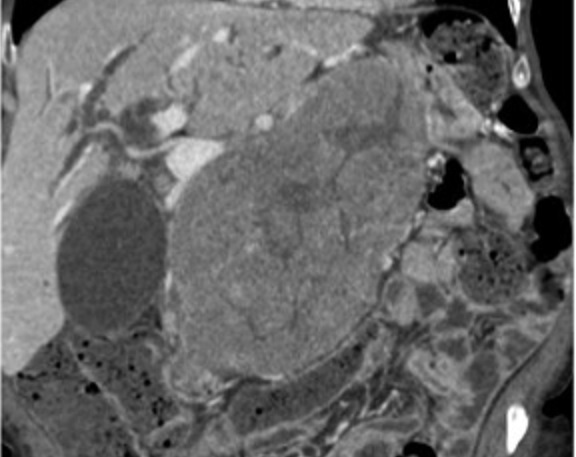

Aspect TDM tres volumineuse

hypodensite heterogen ,bien circoncrite et encapsule

situe du corp pancreas . Sa contenue est non

homogene , rehaussement legere apres injection de

contrast intraveineuse . Image radiologique TDM plus

C+ en coupe axiale phase veineuse |

|

Meme cas en coupe coronale .

La tumeur agresse tres volumineuse a longitudinal du

corp pancreas . |

Une tumeur acinaire tres volumineuse de la tete du

pancreas avec aspect lesionnel d'une masse hypodensite non homogene

, encapsule a bord tres nette ( fleche rouge ) .

Zone de nesrose kystique se retrouve dans 1/3 de la

tumeur . Image radiologique TDM en coupe axilaire |